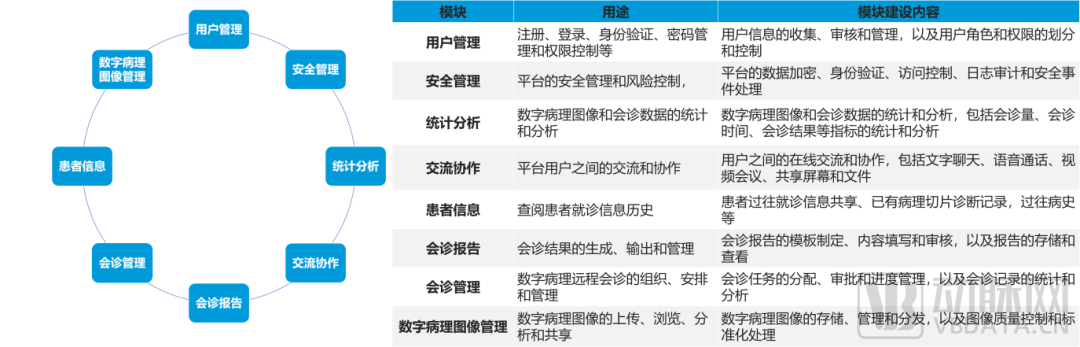

数字化病理科建设模块介绍

数字化建设模块图